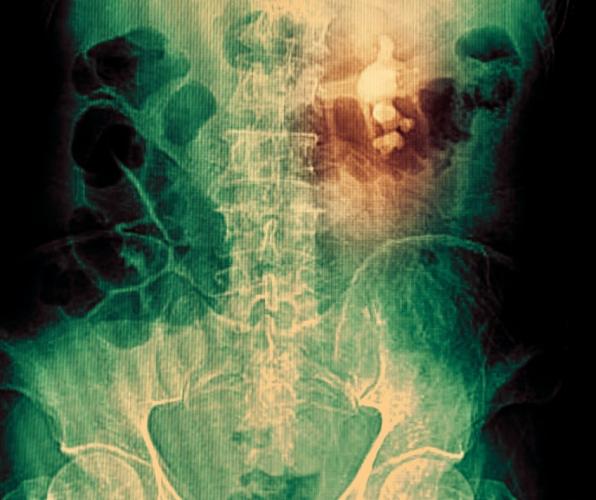

Nephrolithiasis, also called kidney stones or renal calculi, are hard deposits made of salts and minerals formed inside one’s kidney. These are among the most common health problems associated with the urinary system. There are around 600,000 kidney stone cases every year in the United States itself. Where small kidney stones i.e. less than 4mm in size are more likely to pass itself within 31 days, as the size of kidney stone increases it possibility to naturally come out of the body decreases. In such cases, surgical removal is last resort. In this article, we will understand causes, risk factors and symptoms of kidney stones.